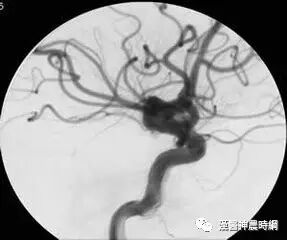

颅内动脉瘤是指脑动脉内腔的局限性异常扩大造成动脉壁的一种瘤状突出,颅内动脉瘤多因脑动脉管壁局部的先天性缺陷和腔内压力增高的基础上引起囊性膨出,是造成蛛网膜下腔出血的首位病因。过去人们称之为先天性脑动脉瘤,事实上先天性脑动脉瘤占脑动脉瘤的70%~80%。

先天性脑动脉瘤好发于脑底动脉环分叉处及其主要分支,约85%的先天性动脉瘤位于Willis动脉环前半环颈内动脉系统,即颈内动脉颅内段,大脑前动脉,前交通动脉,大脑中动脉,后交通动脉的后半部,其中以颈内动脉的虹吸部发生最多,大脑前动脉及前交通动脉次之,大脑中动脉再次之,左右两侧半球发病率相近,右侧稍多于左侧,其中大脑前动脉占4.3%~9.0%,前交通动脉占9.6%~28%;椎动脉占2.3%~4.6%,基底动脉占1.7%~8.9%,综合文献中6570例动脉瘤,其分布情况如下:颈内动脉41.3%,前交通动脉26.1%,大脑中动脉20.4%,大脑前动脉7.6%,椎-基动脉4.6%。

如果动脉壁呈不对称性囊状扩张,即称之为囊状动脉瘤,小的囊状动脉瘤有瘤颈狭窄者又称之为浆果状动脉瘤,绝大多数先天性动脉瘤呈囊状或浆果状,亦可呈小结节状,称之为分叶状动脉瘤,其他形态有葫芦状,圆球状,腊肠状等,瘤壁一般光滑如囊,多数由先天薄弱的血管壁构成,常位于较大动脉的分叉处,动脉瘤与载瘤动脉相连处较狭窄,称为瘤颈(蒂)或基底,瘤颈宽窄很不一致;与瘤颈相对的远侧最突出的部分为瘤底(顶),介于瘤颈与瘤底之间的部位称为瘤体(囊),小阜为瘤囊上小的隆起,常为动脉瘤发生破裂之处或破裂后的遗迹。